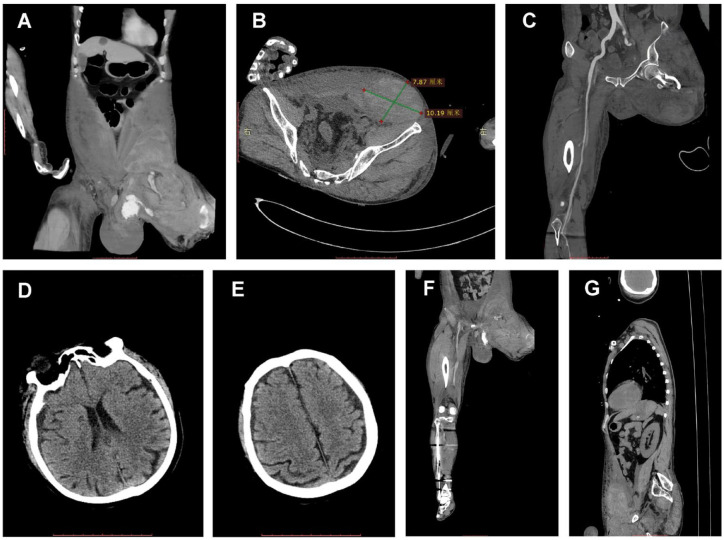

本病例报告详细描述了一名 45 岁男性建筑工人在高处坠落并随后与水泥搅拌机相撞后多处严重受伤的棘手治疗过程。患者出现大面积损伤,包括截肢、骨折和内出血,导致了被称为 "死亡三角 "的状态。尽管最初的预后很糟,ISS评分为28分,死亡风险系数高达89.56%,但通过多学科方法,病人还是被成功地抢救了过来。这包括损害控制复苏、紧急血管干预和有针对性的体温管理以保护大脑。病人的康复突显了综合创伤管理的有效性,以及协调护理在严重多发创伤病例中的关键作用。

This case report details the challenging management of a 45-year-old male construction worker who suffered severe multiple injuries after a fall and subsequent collision with cement mixers. The patient presented with extensive injuries, including amputation, fractures and internal bleeding, leading to a state known as the 'triangle of death'. Despite the initial grim prognosis, evidenced by an ISS score of 28 and a mortality risk coefficient of 89.56%, the patient was successfully resuscitated and managed through a multidisciplinary approach. This included damage control resuscitation, emergency vascular interventions and targeted temperature management for brain protection. The patient's recovery highlights the effectiveness of comprehensive trauma management and the critical role of coordinated care in severe multi-trauma cases.